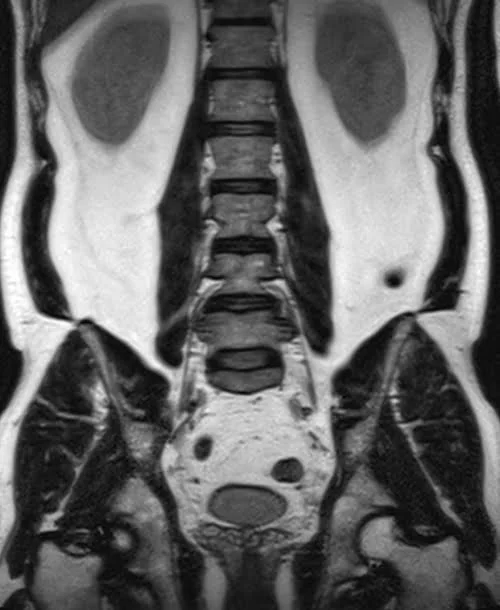

l plexus mri SPACE 3D coronal images